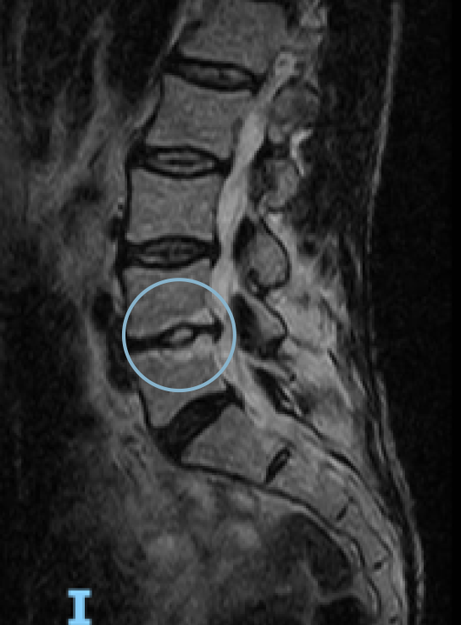

Comparative magnetic resonance imaging of Lumbar spine pre- and one-year post-treatment in a 50-year-old woman diagnosed with lumbar osteoarthritis. The red arrow shows the remodeling of the affected disc

AFTER